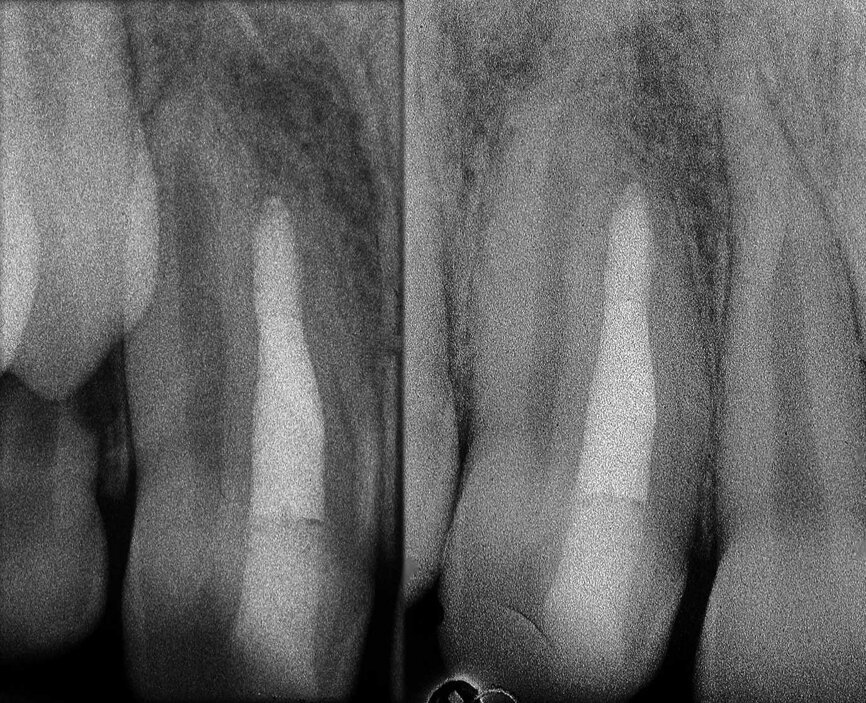

Il en va tout autrement pour la prémolaire mandibulaire présentée dans les figures 7 à 9 où, malgré l’absence de signes radiologiques de lésion et le traitement endodontique visiblement correct réalisé par un autre confrère, le patient se plaint d’une douleur persistante, qui est à la fois spontanée et déclenchée par un test de percussion de la dent. Dans ce cas, l’excellent traitement endocanalaire réalisé précédemment semble indiquer le besoin de recourir à une approche endodontique chirurgicale, susceptible de garantir un taux de réussite plus élevé que celui d’un simple retraitement. Étant donné le doute sur le diagnostic, nous avons décidé de réaliser un examen 3D et celui-ci révèle une lésion endodontique causée par un canal lingual resté sans traitement. Grâce à ce diagnostic exact, il devient possible d’envisager une intervention ciblée sur la pulpe restante, et de réaliser un traitement efficace du canal non traité.